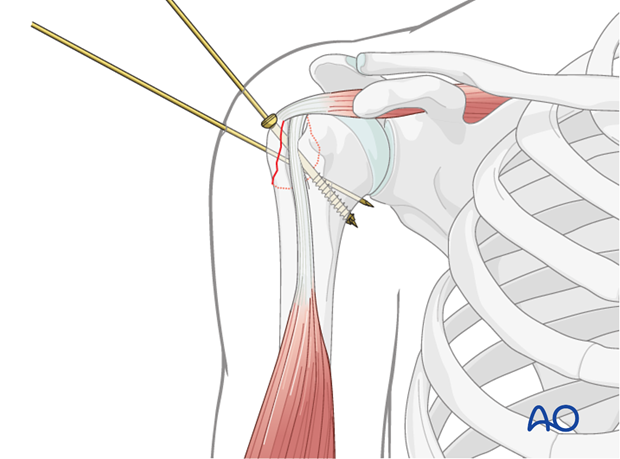

This image illustrates the use of a reduction instrument, likely a pointed reduction forceps, to manipulate and hold the greater tuberosity fragment in its anatomical position prior to definitive fixation.

This image demonstrates the temporary K-wire fixation maintaining the reduced greater tuberosity fragment, a common step before inserting definitive screws.

This image demonstrates the drilling of the pilot hole for screw insertion after reduction and temporary fixation.

This image shows the measurement of screw length after drilling, ensuring appropriate purchase without violating the articular surface.

This image illustrates the final screw insertion, providing stable fixation of the greater tuberosity fragment.